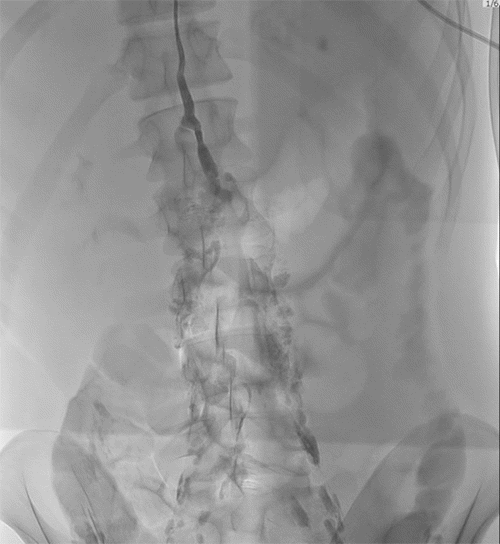

An 18-year-old male with penetrating neck and chest injuries by stab wounds presented to an outside facility. Following chest tube placement for a left hemopneumothorax, he was transferred to our Level I Trauma Center. On arrival, he had a stable Glasgow Coma Scale (GCS) score of 15 and vital signs. Admission to the surgical intensive care unit (ICU) was followed by CT angiography, which demonstrated a left lower lobe parenchymal defect with associated hematoma and pleural effusion (Figure 1).

Figure 1. Initial CTA Showing Pneumothorax and Soft Tissue Emphysema. Published with Permission